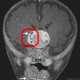

Маленький мальчик из американского штата Мэриленд стал первым в истории медицины пациентом нейрохирургов, у которого в головном мозге выросла редчайшая опухоль с несколькими полностью сформированными зубами в составе.